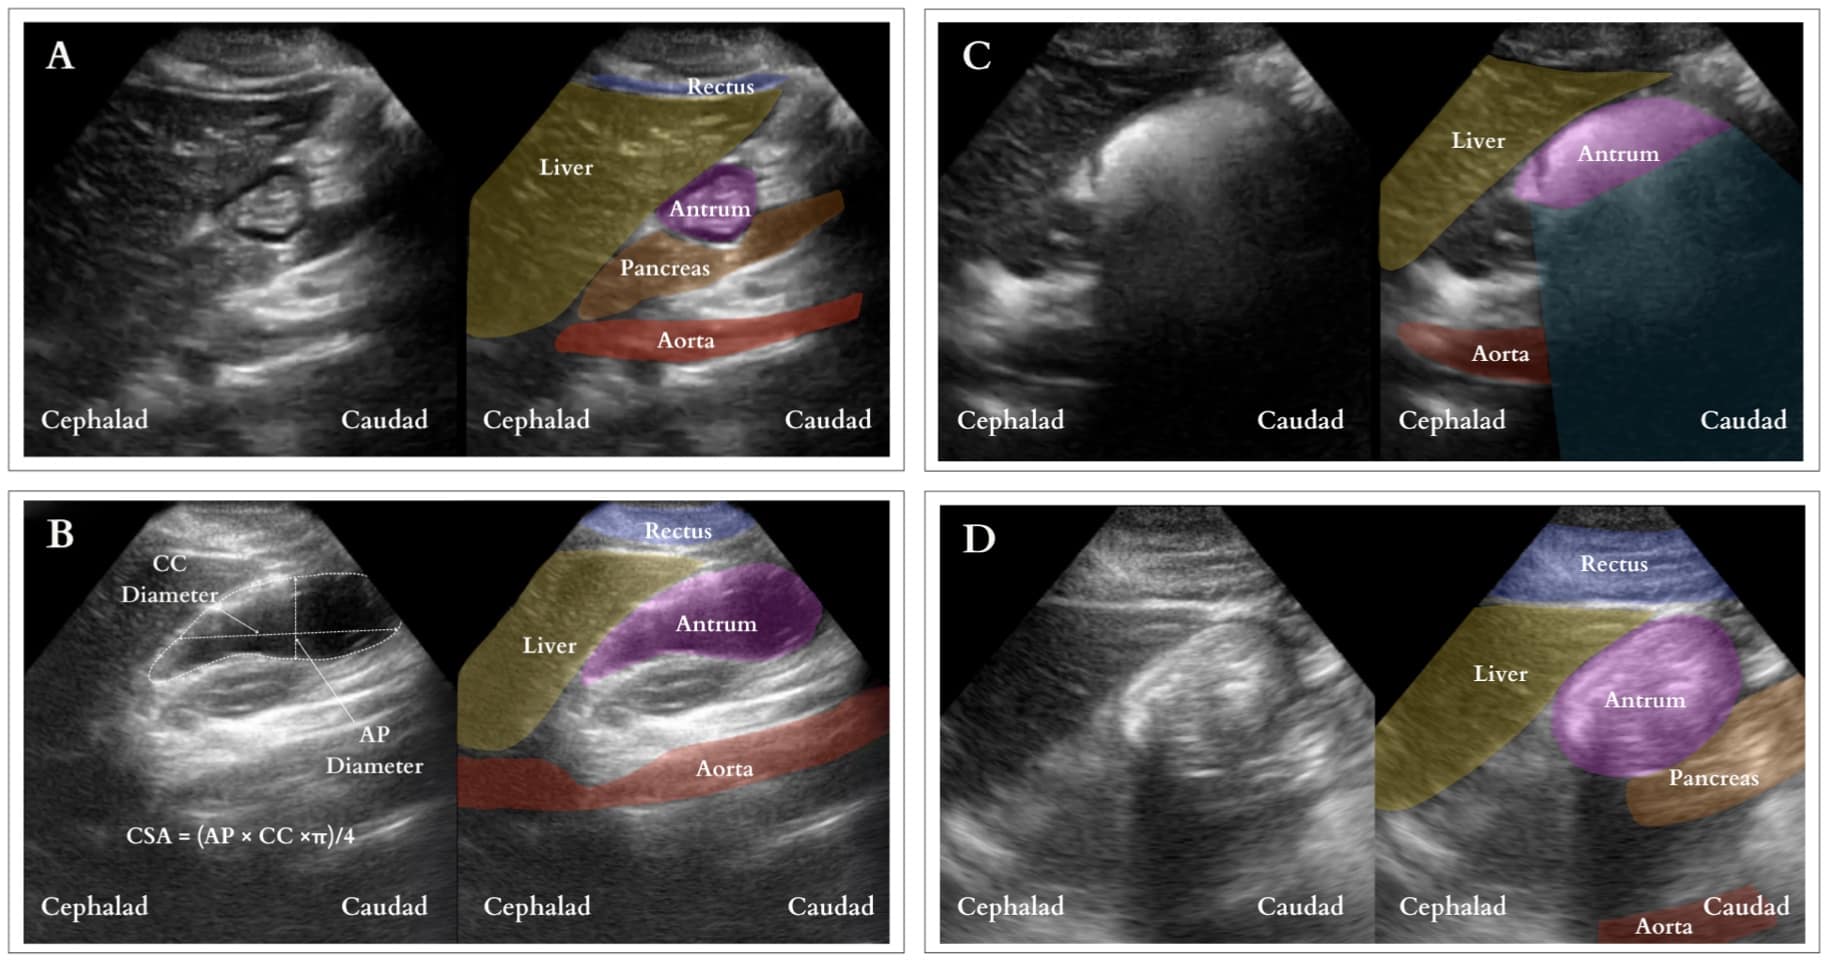

Interpretation (Figure 7): Under ultrasound, the stomach antrum exhibits either empty (Figure 7A) or full states, the latter indicating solid or fluid content. Determining a full stomach with clear fluid involves measuring the cross-sectional area (CSA) of the antrum utilizing the free-tracing method if available or measuring the antral cross-sectional area using the anterior-posterior (AP) and cranial caudal (CC) diameters [CSA = (AP × CC ×π)/4]. (Figure 7B) The CSA is then used to estimate the gastric volume. A volume surpassing 1.5ml/kg is considered above normal. Nonetheless, the threshold for increased aspiration risk remains controversial.12 In contrast, a distended antrum filled with solids exhibits mixed echogenicity with a “frosted-glass” pattern due to the combination of air and solid material post-meal, obscuring the posterior wall and deeper structures (Figure 7C). This distension may persist, with the contents appearing as a compact bolus once most air is expelled (Figure 7D). The presence of solid content confirms a full stomach.

CC = craniocaudal, AP = anteroposterior, CSA = cross-sectional area

Reproduced with permission from baby-blocks.com